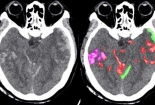

Trí tuệ nhân tạo giúp bác sĩ phát hiện xuất huyết não nhanh hơn